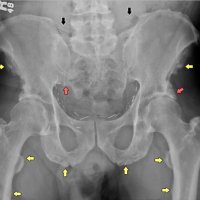

AP radiograph of the pelvis reveals extensive fluffy or "whiskering" enthesopathy of the iliac crests (red arrows), ischial tuberosities (yellow arrows), and the trochanters (black arrows). Note is also made of ossification of the iliolumbar ligament (blue arrow). Importantly, both sacroiliac joints appear normal. These findings are in keeping with diffuse idiopathic skeletal hyperostosis (DISH).

Diffuse Idiopathic skeletal hyperostosis (DISH) is a bone-forming diathesis primarily affecting the spine, with ossification of tendons and ligaments. Most of us are familiar with the spinal findings; however there are extraspinal manifestations as well such as hyperostosis at ligament attachments in the pelvis, calcaneus, tarsal bones, ulnar olecranon and patella.

Usually these are incidental findings without significant morbidity.